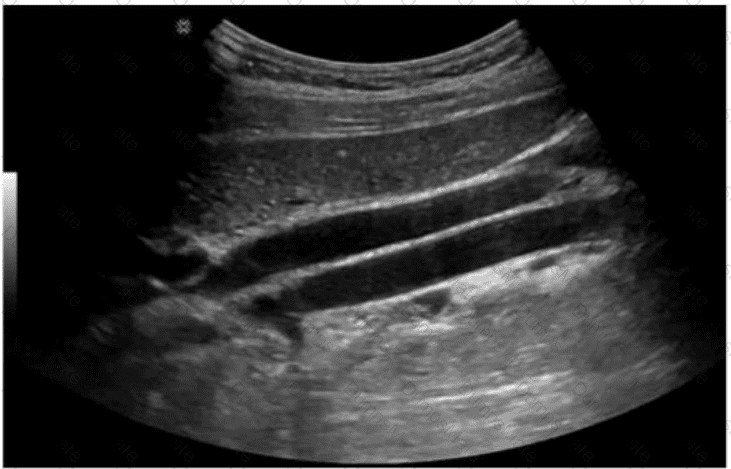

Questions 35

Which portion of the renal arterial vasculature is indicated by the arrow in this image?

AB-Abdomen Question 35

Options:

A.

Interlobular

B.

Arcuate

C.

Segmental

D.

Interlobar